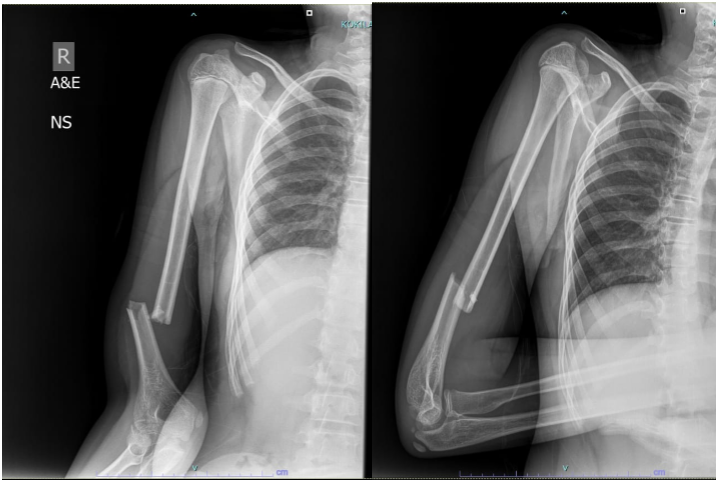

A 13-year-old boy presented in May 2019 with a fracture of the distal third of the right humeral shaft after a fall (Fig. 1).

Figure 1: Initial presentation – distal humeral shaft fracture.

The injury was closed, with no neurovascular deficit. After discussion with the family, he underwent open reduction and internal fixation with plating. The procedure was uneventful, and he was discharged a few days later with intact neurovascular status (Fig. 2).